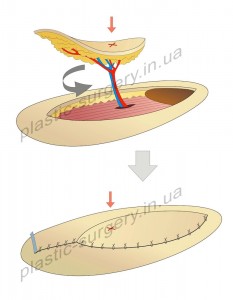

За период с 2008 по 2011 в клинике с целью закрытия дефектов кожи и мягких тканей на конечностях и туловище прооперированы 12 пациентов, у которых выполнено: пять кожно-фасциальных пропеллер лоскутов (PPPF) на перфоранте из басейна локтевой артерии (UAP), два торакодорзальных лоскута с транспозицией по типу пропеллера (TDAP), один лоскут (PPPF) на базе перфорантной артерии из басейна задней большеберцовой артерии (PTAP), четыре латеральных надлодыжечных лоскута на перфорантной кожной ветви малоберцовой артерии (PNAP). Параметры лоскутов представлены в таблице 1.

Таблица 1.

Перфорантные пропеллер лоскуты на ножке (PPPF) и их параметры.

Все пациенты выздоровили и были выписаны из клиники. В качестве осложнений, свойственным многим видам лоскутной пластики, у наших пациентов с пропеллерными лоскутами наблюдались: отек во всех случаях, продолжительностью до 3 суток; венозный застой на ограниченных участках лоскутов в четырех случаях; подлоскутная гематома с имбибицией лоскута в одном случае; частичная краевая утрата дистальноно отдела лоскута в четырех случаях, два из которых были обусловлены инфекционной атакой с лизисом подкожной клетчатки и кожи. Полной утраты лоскутов в результате тромбоза питающей артерии или каких либо других причин, в рассматриваемых случаях отмечено не было. В случаях венозного застоя для предотвращения некроза застойного участка лоскута местно применялись препараты, обладающие вазадиллятирующем действием (папаверин, нитроглицерин), гирудотерапия, гепаринизация лоскута («химические пиявки»), вибромассаж лоскута. В случае развития гематомы под лоскутом на третий день была произведена ревизия раневого ложа с гемостазом и адекватным дренированием подлоскутного пространства. В случаях частичной утраты дистального отдела лоскута потребовалось наложение вторичного шва в 3 случаях после иссечения зоны дистального краевого некроза. Все эти осложнения не носили критического характера и были разрешены, что потребовало несколько большего времени пребывания в клинике.

Применение пропеллерных лоскутов позволило нанести минимальный урон донорской зоне, которая во всех, кроме одного, случаях была ушита и зажила первичным натяжением. В одном случае была необходимость дополнительного закрытия донорского ложа расщепленным кожным трансплантатом – при значительном размере надлодыжечного лоскута. Перемещенные в область раневого дефекта пропеллер лоскуты были схожи по структуре и окраске с окружающими тканями. Они не изменяли контуры реципиентной зоны и одновременно позволяли воссоздать полноценный износостойкий мягкотканный и кожный покров, восстановить функциональное состояние поврежденного участка тела с минимальным эстетическим ущербом.